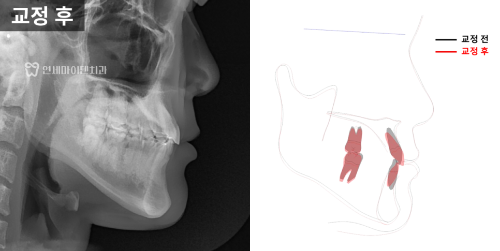

3급 부정교합 진단

방사선 사진을 분석해 보니

위턱보다 아래턱이 발달한 3급 부정교합,

흔히 '주걱턱'이라고 하는 상태였습니다.

아래 앞니의 각도가

정상치보다 훨씬 작은 68.7도로

안쪽으로 쓰러져 있었습니다.

최종 치료 결과

최종적으로 위아래 치아는 가지런하게 배열되었고

옆모습에서는 턱끝이 덜 돌출돼

개선된 인상을 주었습니다.

교정으로 교합과 악궁을 변화시키면서

턱 위치가 약간 아래로 회전

이런 효과가 나타난 것입니다.